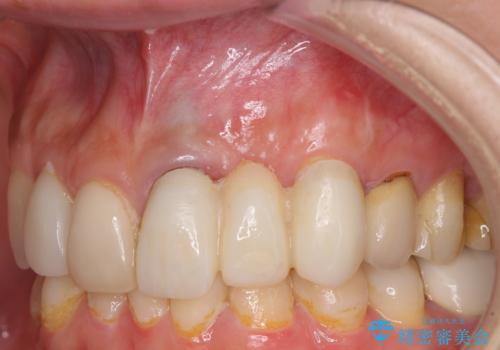

歯肉移植を用いた前歯のオールセラミックブリッジ

インプラントかブリッジか悩むところでしたが、既に治療されている前歯のクラウン周りの変色が気になっていたため、ブリッジにより色調を合わせたオールセラミックを装着することを選択しました。

歯肉ラインや歯の形態、色調を整えることができ、患者様には大変満足していただきました。